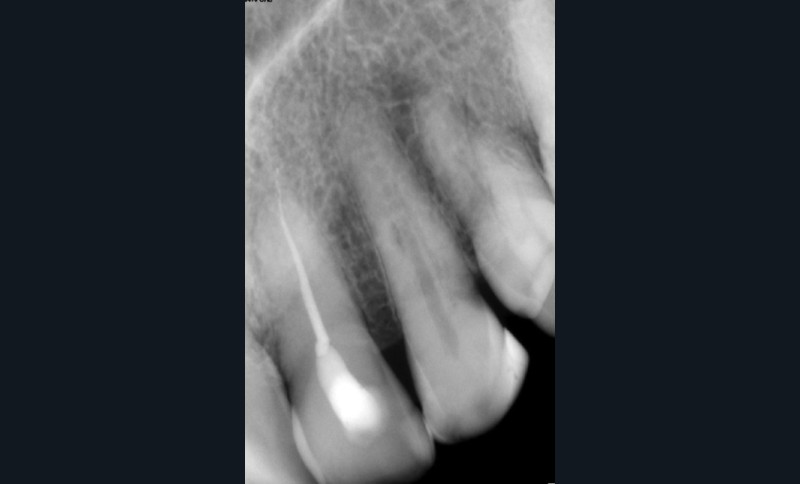

Le passage du laser est répété plusieurs fois, en début, au milieu et en fin de préparation. Un protocole peut alors être proposé : 40 mJ ; 20 Hz (fig. 7). L’utilisation de biocéramiques Bioroot (Septodont) ou Total Fill R (FKG) permet de sceller le système ainsi nettoyé, en assurant une action biologique de longue durée [46] (fig. 8a à c).